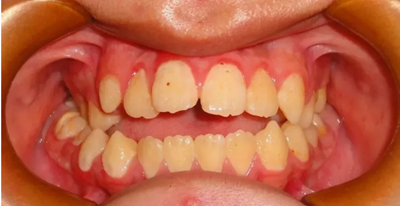

04 開合

因經(jīng)常吃不了瓜子,口腔不能執(zhí)行撕咬的動作或食物咬不斷前來就診,該如何避免?